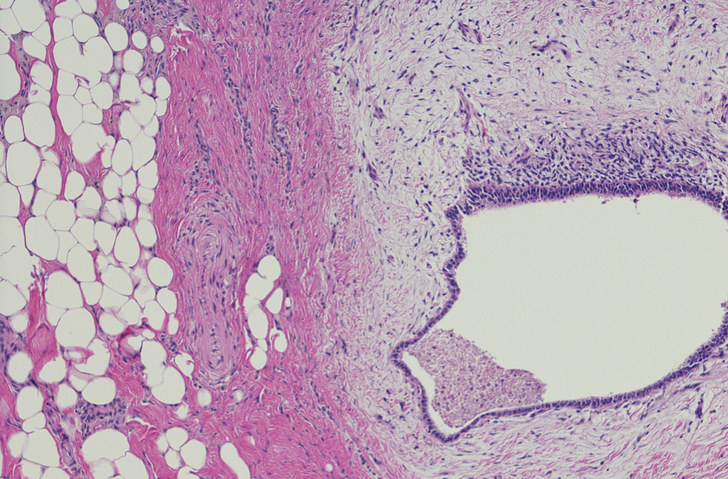

5. Your organs are mangled.

"Your ovaries are mangled."

From the surgeon who had just operated on said ovaries. Endometriosis is a complex condition which needs specialist surgeons; however, lack of funding, training and research means generic OBGYNs will undertake surgery, often with poor outcomes. I cannot state this enough — do your research and get an endometriosis specialist.

8. You probably have cancer.

The first time I was hospitalized, I didn’t even know what endometriosis was. I was 18 and was admitted because I had a cyst the size of a lime on my left ovary that was bursting, and a cyst the size of a CD growing on my right ovary. My doctor came into my room and promptly said, “Well, we’re probably going to take out one or both ovaries, and there’s a 50/50 chance it’s cancer. Alright? Any questions?” I said, "no" and he left.

10. All women get cysts.